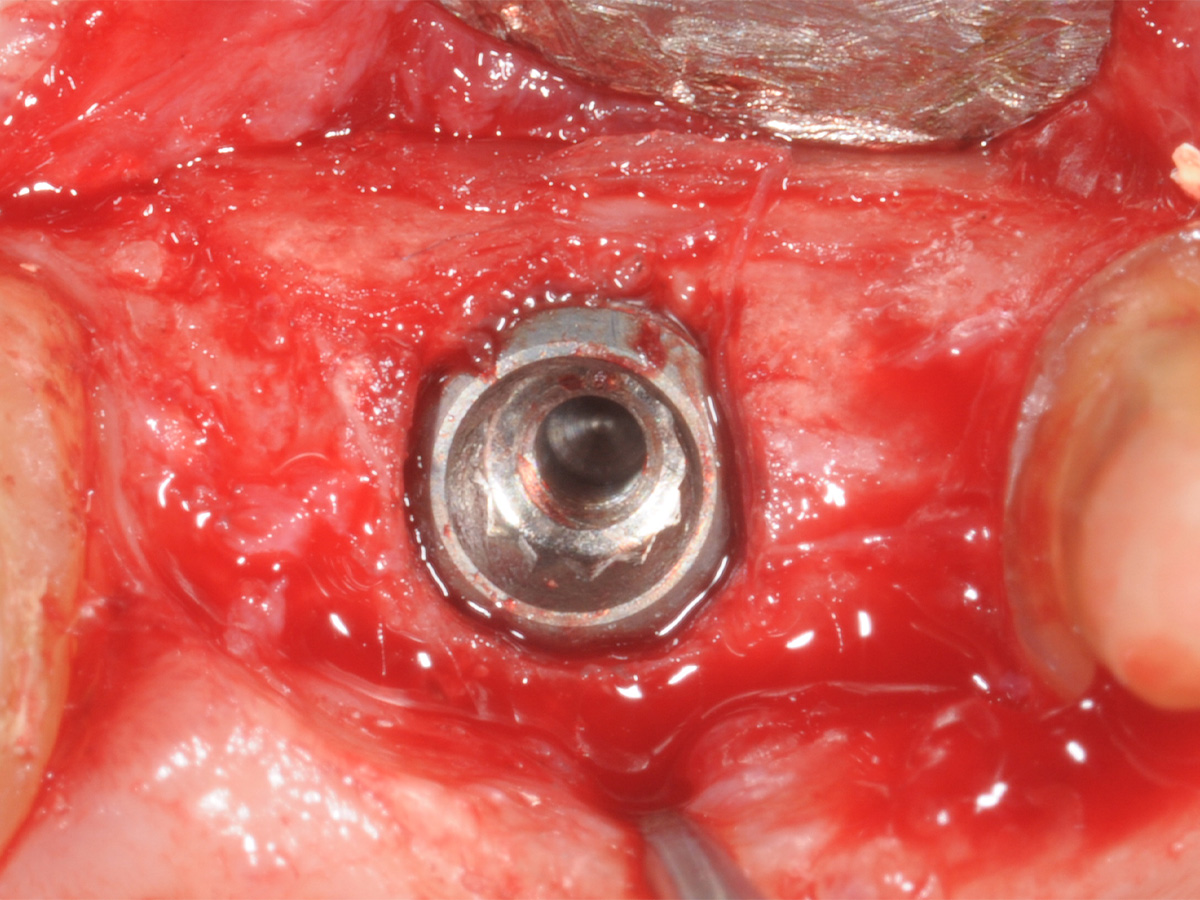

Abbildung 12

Implantation: Gutes Knochenvolumen in horizontaler und vertikaler Dimension.

Abbildung 13

Implantation in optimaler prothetischer Ausrichtung möglich, da ausreichendes knöchernes Angebot in vertikaler und horizontaler Dimension.